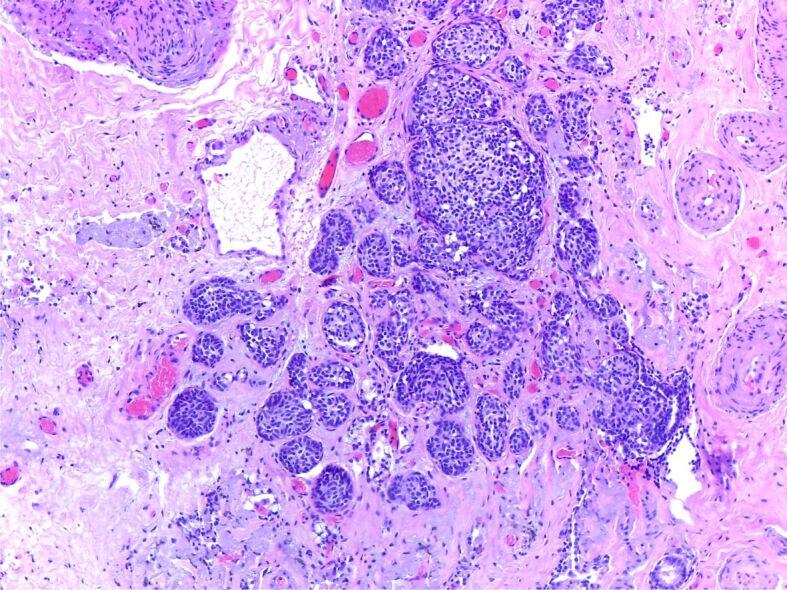

The most challenging cases encountered during the recent years were those of lung hamartoma associated with eosinophilic pneumonia because of the multicentricity of the disease and the suspicion for metastasis in the clinical setting, pulmonary aspergillosis that presented as a cystic lesion with a 9 mm mural nodule, actinomycosis discovered as firm nodule showing aspects of false pleural invasion, cryptococcosis - a hilar mass for which a pneumectomy was prepared, pulmonary parasitosis that presented as a nodule with irregular borders, causing pleural retraction, one case of inflammatory myofibroblastic tumor of the lung, one case of tumorlet type neuroendocrine lesion in a patient with history of melanoma and renal oncocytoma, admitted under the suspicion of lung metastasis.

近年来遇到的最具挑战性的病例是肺错构瘤伴嗜酸性肺炎,因为疾病的多中心性和临床环境中对转移的怀疑,表现为囊性病变伴 9 毫米壁结节的肺曲霉病,表现为假性胸膜侵犯特征的坚实结节的放线菌病,准备进行肺切除术的隐球菌病 - 肺门肿块,表现为不规则边界结节导致胸膜回缩的肺寄生虫病,一例肺部炎性肌纤维母细胞瘤,一例黑色素瘤和肾嗜酸细胞瘤病史患者的肿瘤样神经内分泌病变,怀疑为肺癌转移而入院。